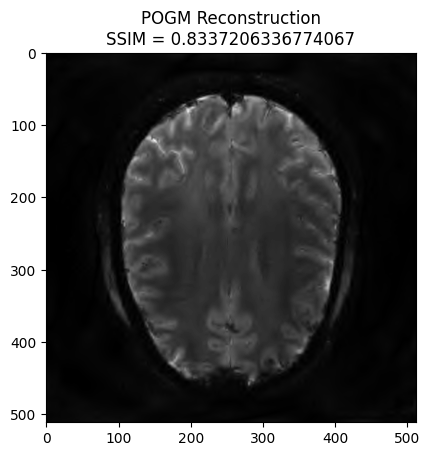

POGM reconstruction#

x_final, costs, metrics = reconstructor.reconstruct(

kspace_data=kspace_obs,

optimization_alg='pogm',

num_iterations=200,

)

image_rec = pysap.Image(data=np.abs(x_final))

recon_ssim = ssim(image_rec, image)

plt.imshow(np.abs(image_rec), cmap='gray')

plt.title('POGM Reconstruction\nSSIM = {}'.format(recon_ssim))

plt.show()

- mu: 1e-08

- lipschitz constant: 16.206116

- data: (512, 512)

- wavelet: <mri.operators.linear.wavelet.WaveletN object at 0x7e8282f94a00> - 4

- max iterations: 200

- image variable shape: (1, 512, 512)

----------------------------------------

Starting optimization...

- final iteration number: 200

- final log10 cost value: 6.0

- converged: False

Done.

Execution time: 530.4063913400023 seconds